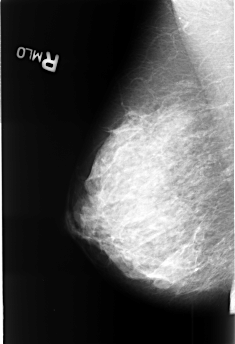

B_3390_1.RIGHT_MLO

RIGHT_CC LINES 4456 PIXELS_PER_LINE 3056 BITS_PER_PIXEL 12 RESOLUTION 50 NON_OVERLAY

RIGHT_MLO LINES 4472 PIXELS_PER_LINE 3048 BITS_PER_PIXEL 12 RESOLUTION 50 NON_OVERLAY